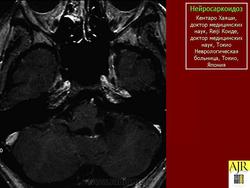

Грег А. Christoforidis, Эрик М. Spickler, Мария Владимировна Ресио и Бхарат М. Мехта

Рисунок 8

Рисунок 8 Нейросаркоидоз.